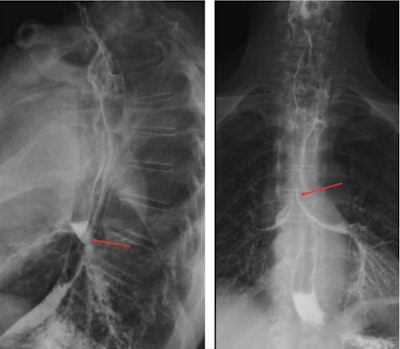

He underwent a barium swallow fluoroscopy that revealed an irregularity of the esophageal tract, aspiration of contrast on swallowing, and findings of an esophageal mass. A computed tomography (CT) scan of the man's neck, thorax, abdomen, and pelvis with contrast reported esophageal wall thickening, suggesting a fistula between the esophagus and proximal trachea. Also, there was shadowing indicative of an infection, they wrote.

Preoperative barium swallow fluoroscopy study. Shows contrast in the trachea and esophagus (red arrows), suggesting a fistulous communication. Images and captions courtesy of Dr. Hannah Jesani, et al. Licensed under CC BY 4.0.